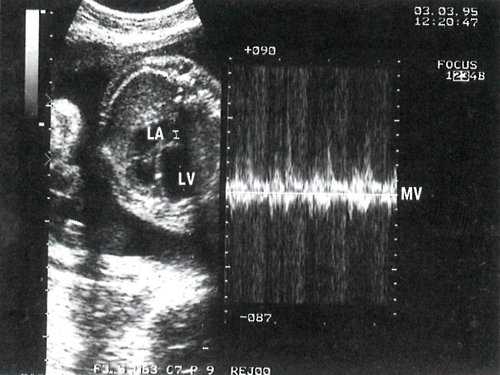

Степень раскрытия створок (3 мм) и кровоток через митральный клапан значительно уменьшены (рис. 3).

Рис. 3. В-сканирование на уровне четырехкамерного сечения и допплеркардиография потока через митральное отверстие. Контрольный объем расположен под створками митрального клапана. LA - левое предсердие.